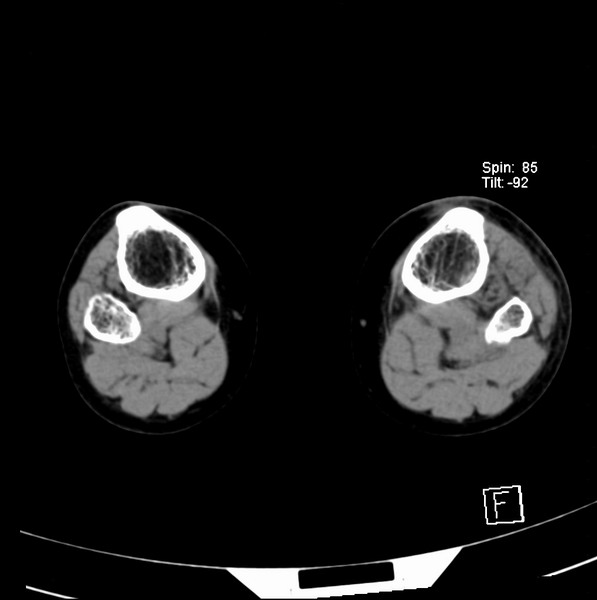

标题: CT21917:右腓骨小头是否骨软骨瘤? [打印本页]

标题: CT21917:右腓骨小头是否骨软骨瘤?

女、43.

不是骨软骨瘤,“牵拽征”,正常变异。有平片吗?

正常变异,“牵拽征”,比目鱼肌牵拽.